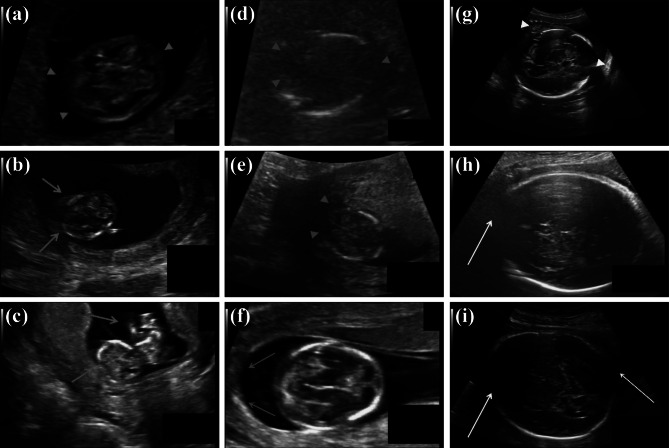

Fig. 1.

Representative fetal ultrasound images at different trimesters of pregnancy. a–c First trimester (blurred fetal head indicated by red arrow heads, artifacts indicated by red arrows). d–f Second trimester (low signal-to-noise ratio indicated by blue arrow heads, bright reflection from the interface of the fetal membranes (attached to the uterine wall) and the amniotic fluid indicated by blue arrows). g–i Third trimester (speckle noise indicated by yellow arrow heads, interruption of the fetal skull by the normal sutures or ultrasound artifacts indicated by yellow arrows)